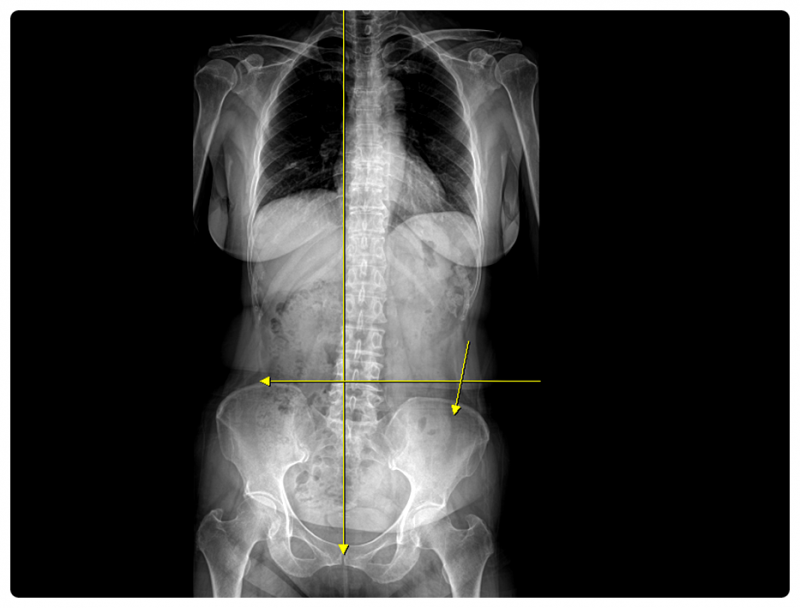

무릎 관절 자체의 문제가 아니라 발목 정렬이 틀어져 있거나, 골반이 한쪽으로 기울어지며 부담이 누적된 경우도 적지 않습니다.

그래서 저는 통증이 있는 부위만 살피기보다, 원인이 되는 ‘가해자’가 어디에 있는지부터 찾는 과정을 중요하게 보고 있습니다.